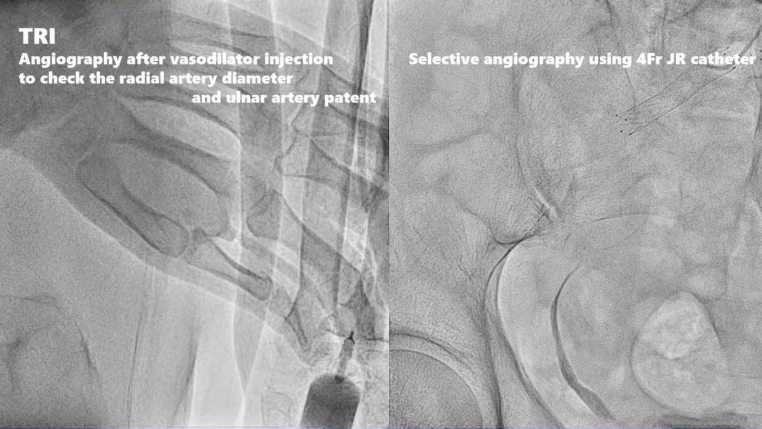

1、使用血管扩张剂注射后的血管造影,以检查桡动脉直径和尺动脉通畅性,使用4Fr JR导管进行选择性血管造影。